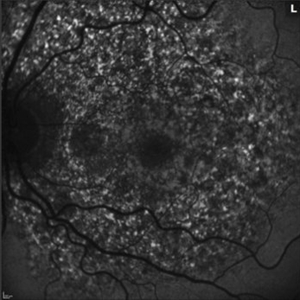

Retinal Vasculitis in Behcet's OS

Retinal Vasculitis in Behcet's OS

Jun 29 2018 by Gareth Lema, MD, PhD

IVFA at 7 minutes showing retinal vasculitis, cystoid macular edema, and disc staining.

Photographer: Ross Eye Institute, University at Buffalo Jacobs School of Medicine, Buffalo. NY

Imaging device: Optos

Condition/keywords: Behcet's Disease, cystoid macular edema (CME), disc staining, retinal vasculitis